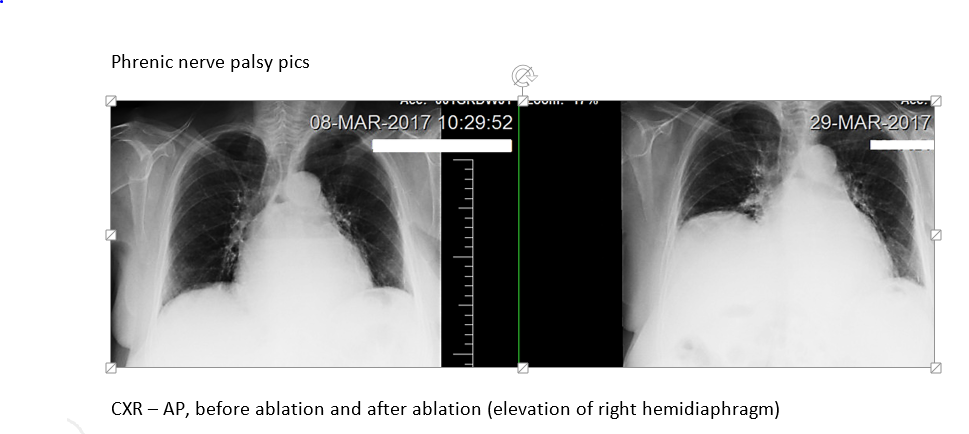

A 77-year-old Caucasian female presented with dyspnea and chest pain for 8 days. One week ago, she had undergone radiofrequency catheter ablation for persistent symptomatic AF. PMH included heart failure with preserved ejection fraction and mild COPD. She led an active lifestyle, did not require oxygen, and had quit smoking 10 years ago. After the ablation, she reported dyspnea even during office visits, which were attributed to heart failure. She had been given increasing doses of diuretics which did not relieve her symptoms. On physical exam, she was in mild distress. Pulse oximetry was 90%. Her weight had not increased and she had no clinical signs of heart failure. Laboratory work up revealed WBC of 10,000, normal electrolytes and negative troponin. ABG showed paO2 of 62 mm Hg and EKG did not reveal signs of ischemia. CXR demonstrated a grossly elevated right diaphragm. Sniff test performed under fluoroscopy showed paradoxical elevation of the right hemidiaphragm with inspiration, compared with rapid descent of the left hemidiaphragm, confirming right hemidiaphragm paralysis. Patient’s dyspnea was proportionate to the degree of physical activity and hence she did not need treatment by surgical plication. She was discharged with home oxygen. She has remarkably improved and her symptoms have resolved.